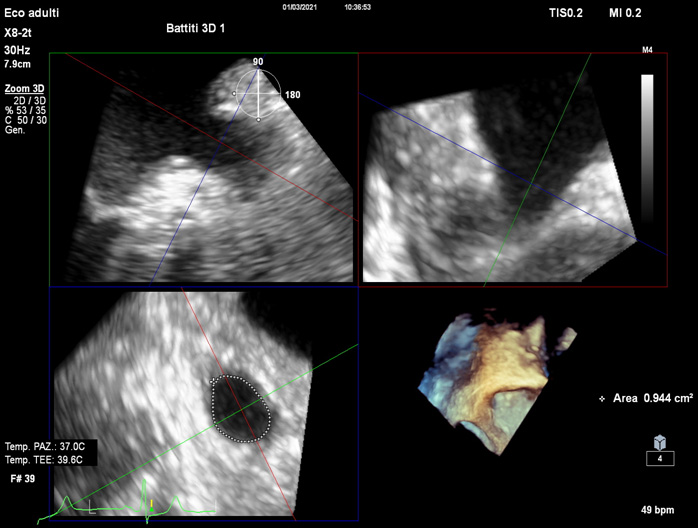

Although 2D TOE represents the routinely modality for pre-operative assessment, the use of 3D TOE gives practical additive information in identifying uncommon morphologies [12], and its use is increasing. While its anatomic estimations are superior to 2D TOE, slow temporal resolution of 3D TOE and lacking professional guidelines still represent limitations of this technique.

Detailed characterization of the LAA body and orifice shapes can facilitate device selection (Fig. 5).

Fig. 5.The use of 3D TOE provides useful additive evaluation about unusual morphology or irregular orifices.